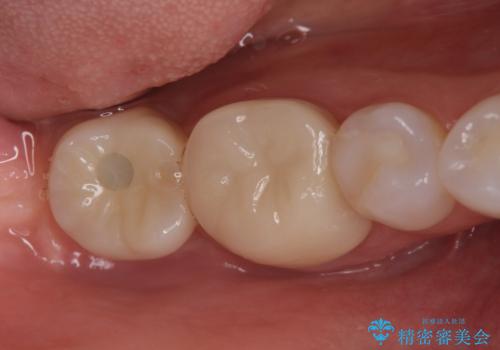

通常このような場合、神経を除去し歯を短くしたのちインプラント治療を行いますが、今回はマイクロインプラントを用いて歯を歯ぐきの方向へ沈めたのち神経を温存する形でインプラント補綴を行いました。

伸びてしまった上の奥歯を、神経もとらず、クラウンにもせず治療することができ、喜んでいただくことができました。